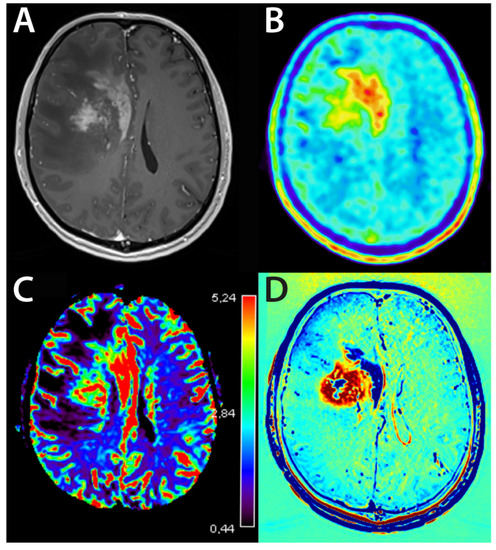

4.3. Nuclear Medicine—PET

4.3.2. 18F-FET—PET